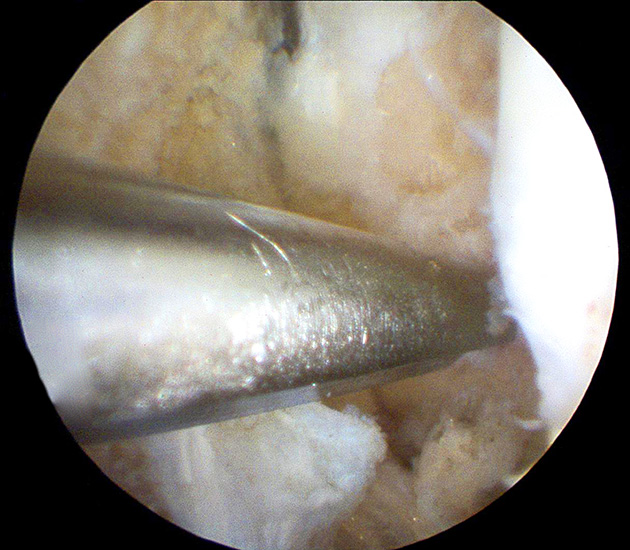

- Arthroskopisches Fadenholinstrument (Abbildung 1) oder eine gebogene kanülierte Ahle mit einer Drahtschlaufe (Abbildung 2).

Operationstechnik

Nachfolgend wird die OP-Technik an einem rechten Sprunggelenk unter Verwendung von PEEK-Ankern veranschaulicht.